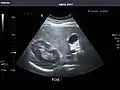

Abdominal ultrasound can be used to diagnose abnormalities in various internal organs, such as the kidneys,[1] liver, gallbladder, pancreas, spleen and abdominal aorta. If Doppler ultrasonography is added, the blood flow inside blood vessels can be evaluated as well (for example, to look for renal artery stenosis). It is commonly used to examine the uterus and fetus during pregnancy; this is called obstetric ultrasonography.[2][3]

- ↑ Whitworth M, Bricker L, Mullan C (July 2015). "Ultrasound for fetal assessment in early pregnancy". The Cochrane Database of Systematic Reviews. 2015 (7): CD007058. doi:10.1002/14651858.CD007058.pub3. PMC 4084925. PMID 26171896.

- ↑ Salomon LJ, Alfirevic Z, Bilardo CM, Chalouhi GE, Ghi T, Kagan KO, et al. (January 2013). "ISUOG practice guidelines: performance of first-trimester fetal ultrasound scan". Ultrasound in Obstetrics & Gynecology. 41 (1): 102–113. doi:10.1002/uog.12342. PMID 23280739.